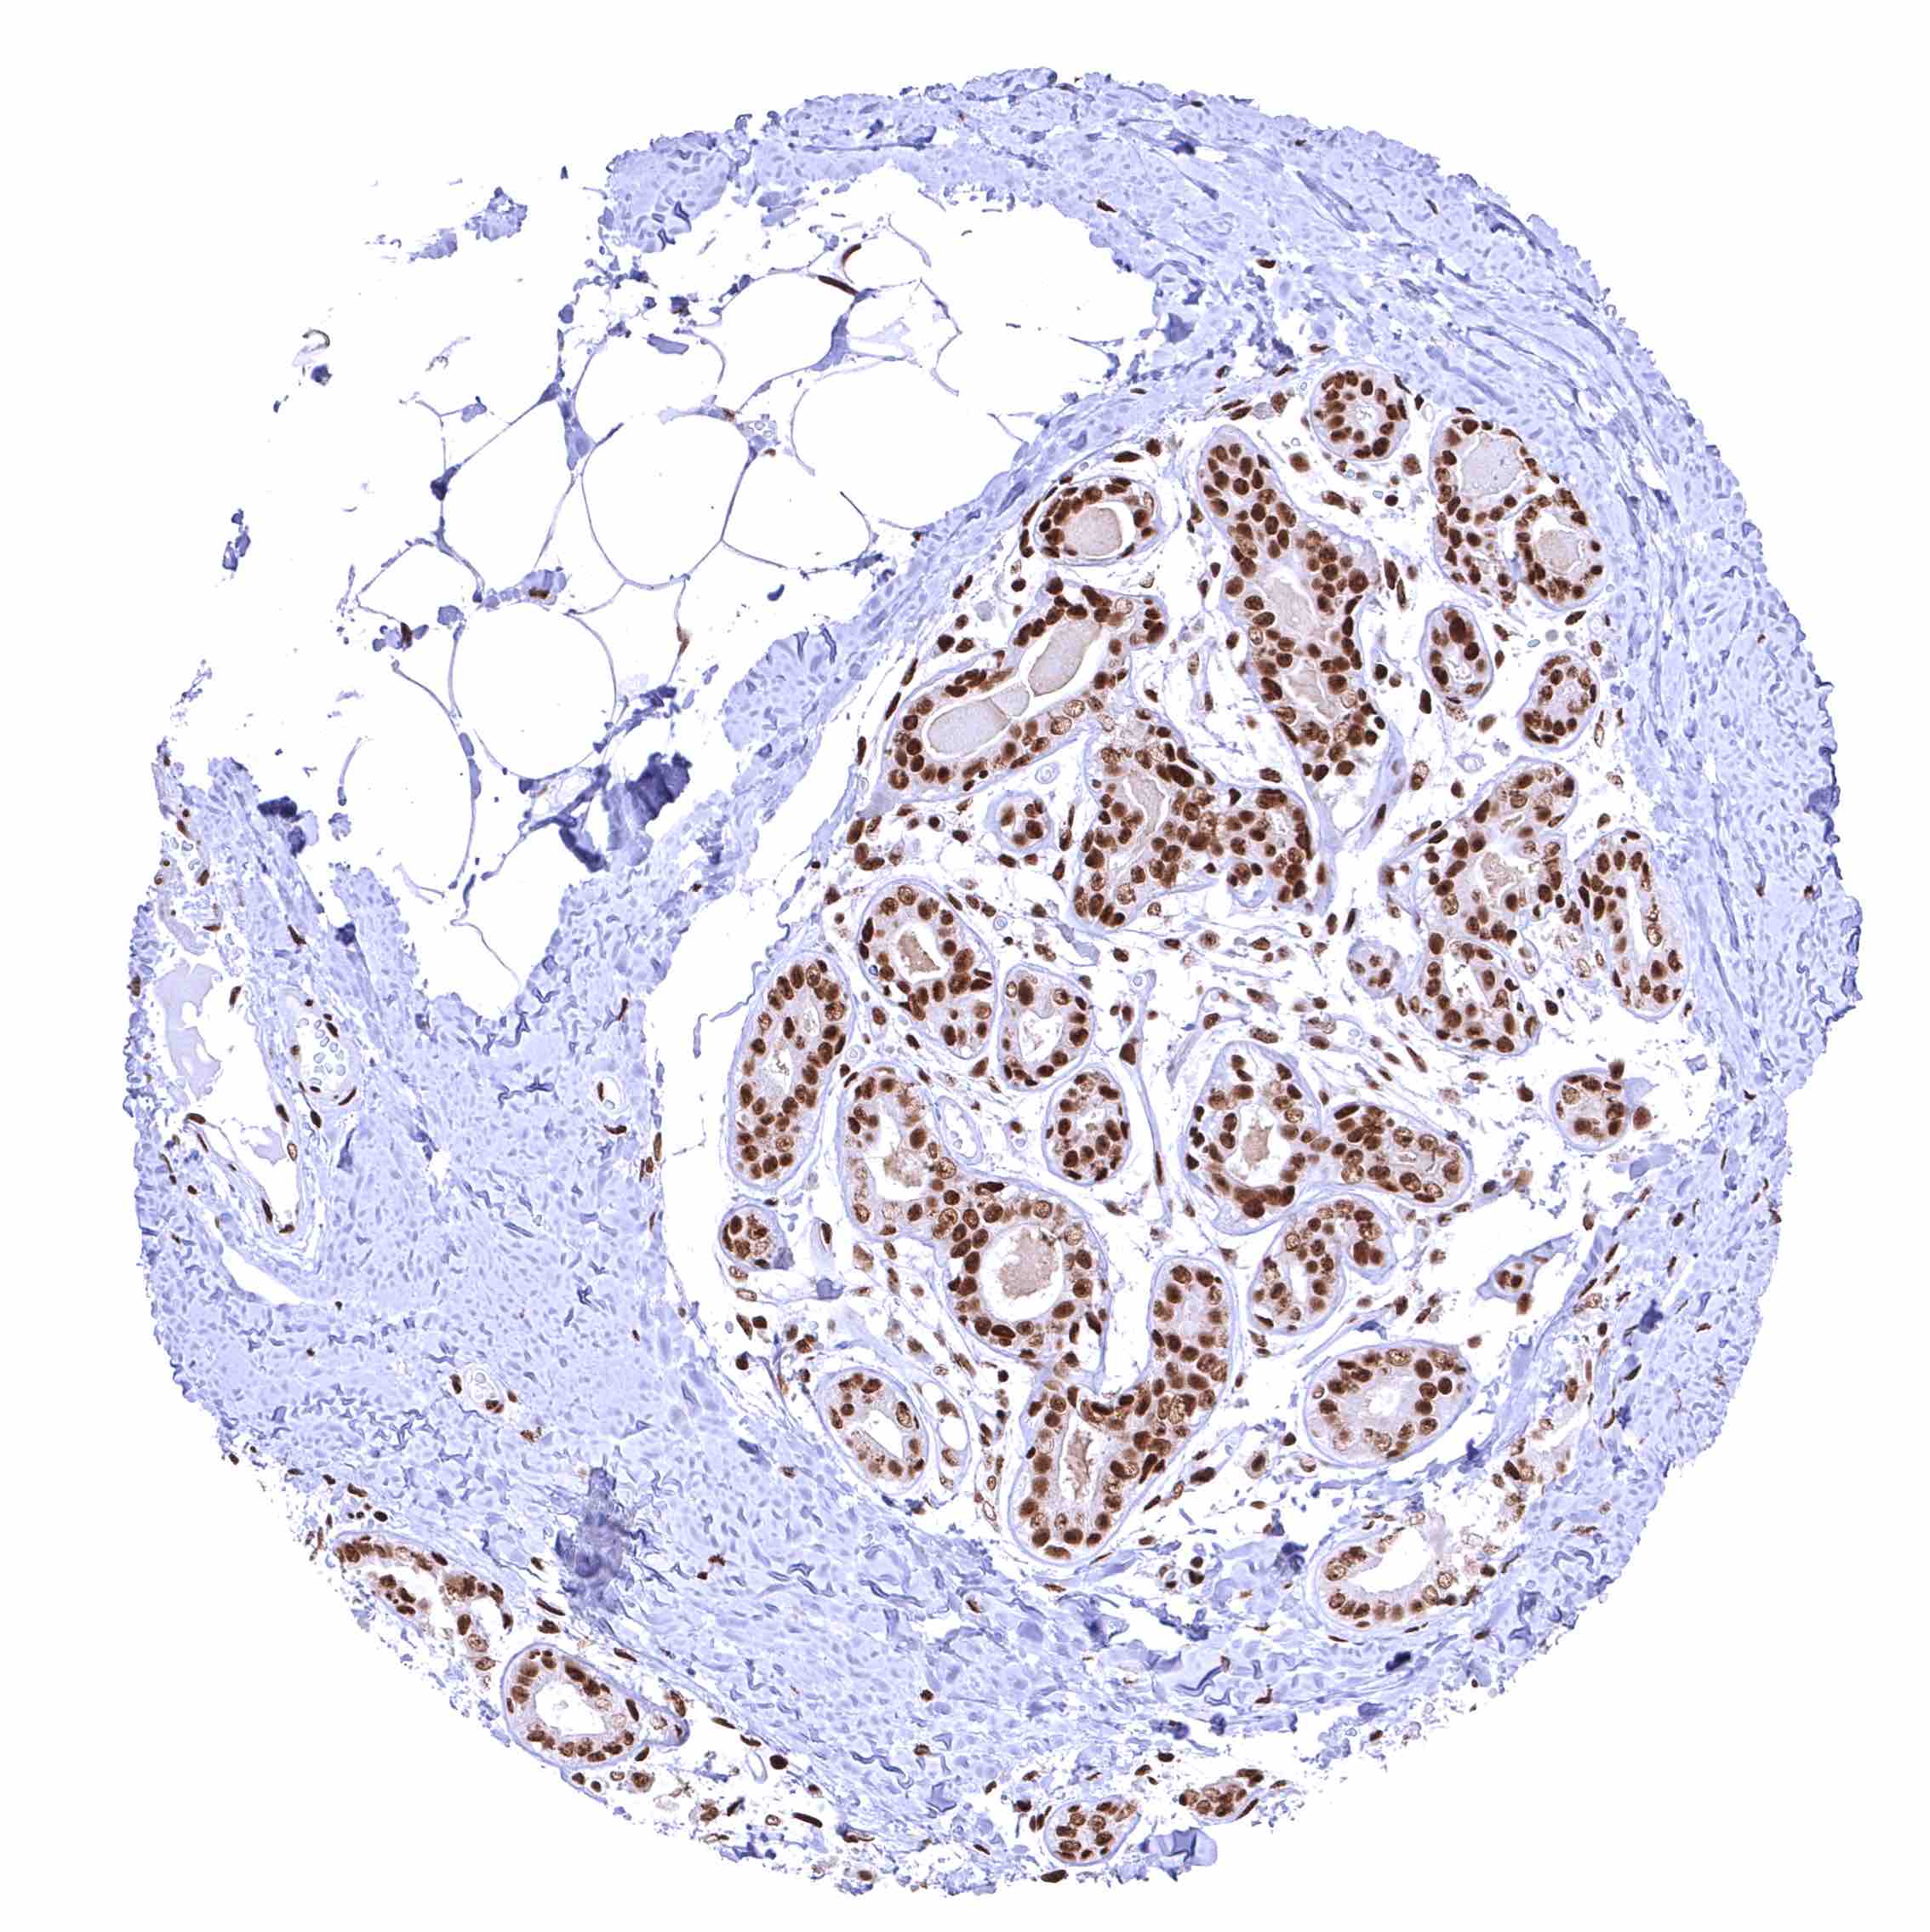

Breast – Distinct nuclear BRD4 staining of epithelial cells.

Prostate – BRD4 staining of basal cells is somewhat stronger than of acinar cells.